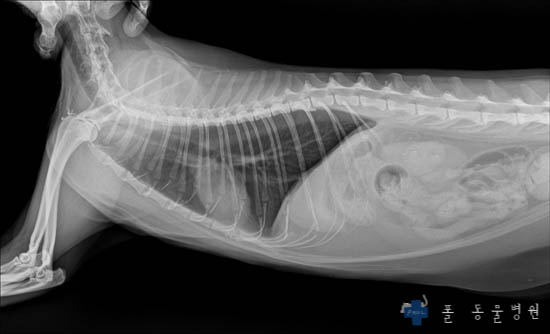

그러면 Xray 촬영을 하게 되는데요.

몸의 골격계, 내부 장기의 형태, 호흡기계 등을 평가하는 중요한 검사입니다.